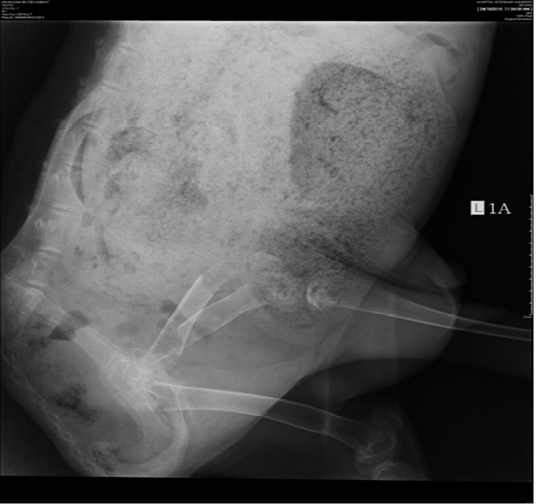

Figure 1

Discontinuity of the left femur bone at the mid-femoral region on left-lateral view.